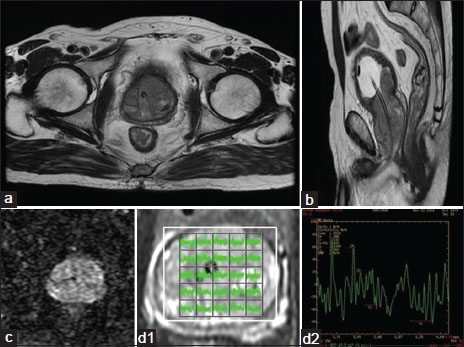

| Figure.5:Transition zone Carcinoma. (a) T2W axial image showing ill-defined hypointensity involving predominantly left transition zone. (b) Sagittal image of the same. (c) Focal area of restricted diffusion. (d) MRS shows elevated choline and reduced citrate peak